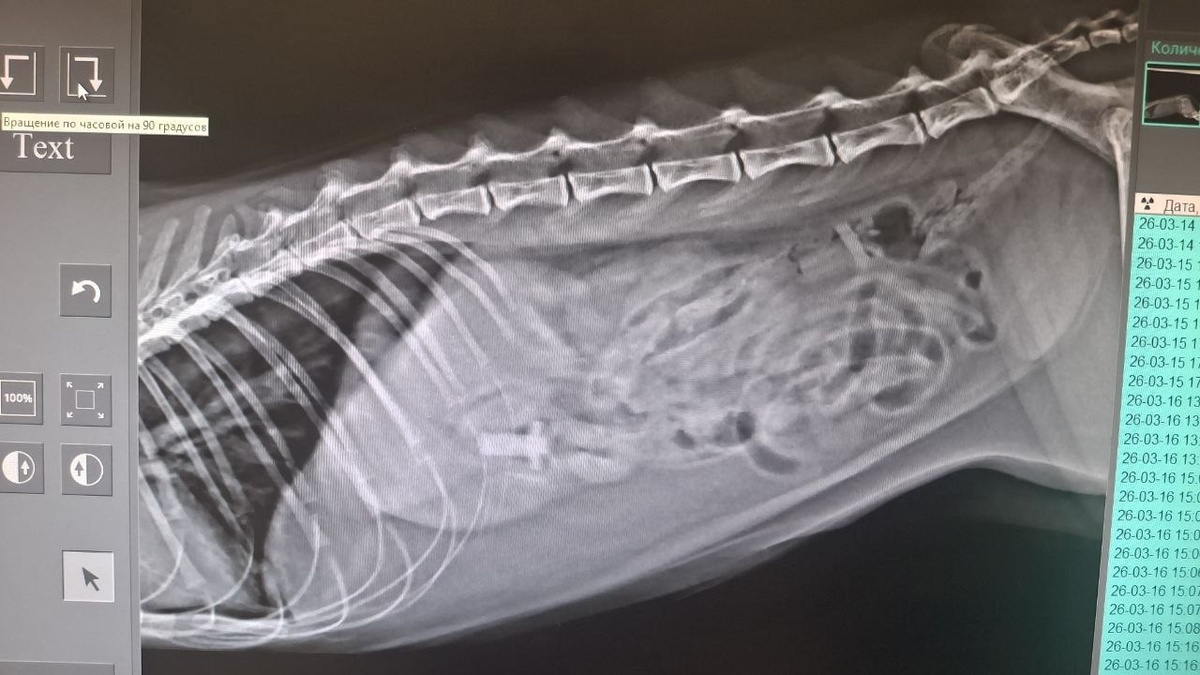

Позвонила клиентка, кота рвёт. Плохо ест, но воду пьет, бодр и весел. До этого играл с пульками от игрушечного пистолета. Пульки нашли на рентгене. Проблема не только в пластиковой части, а ещё и в пороллоновом «хвосте», который не даёт этой пульке продвигаться по кишечнику. Обошлись малой кровью (но приличной ценой). Достали в клинике пульки эндоскопом. Без разрезов. Одну через «вход», вторую через «выход».

Пульки нашли на рентгене. Проблема не только в пластиковой части, а ещё и в пороллоновом «хвосте», который не даёт этой пульке продвигаться по кишечнику.